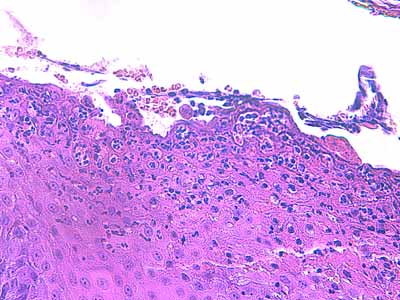

Photo 12 (Hémalun-Eosine X400) : Vue rapprochée du plancher d’une

pustule intra-épidermique sous-cornée : forte exocytose de granulocytes éosinohiles;

quelques cellules épithéliales s’arrondissent et se libèrent de leurs attaches

desmosomiales, rappelant une acantholyse intra-épidermique.

Légendes de la Photo 12 :

- Étoiles rouges : cellules épithéliales se détachant individuellement ou en petits groupes du plancher épidermique, leurs contours cytoplasmiques sont lisses, arrondis et leur noyau non pycnotique, suggérant une acantholyse intra-épidermique

- Étoiles vertes : granulocytes

- Double flèche noire : épiderme

- Flèches oranges : exocytose granulocytaire au sein du plancher épidermique conduisant à la formation de micro-pustules